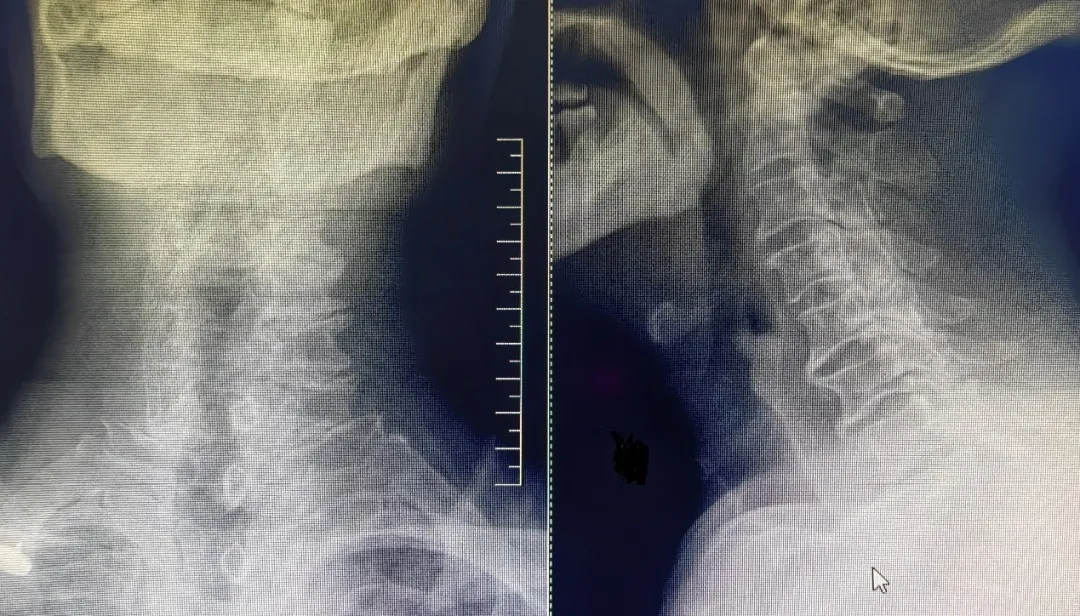

患者,男性,左上肢内侧疼痛剧烈,保守治疗无效,就诊于91直播 脊柱外科中心B区,诊断为神经根型颈椎病,C7/T1节段,左侧神经根管骨质增生严重,颈前路手术因胸骨阻挡难以实施,后路手术减压风险高、担心减压不彻底且创伤大。赵文奎博士了解患者病情后,用北医三院的诊疗理念,从影像学资料研判、诊断与鉴别诊断、治疗方案的制定等不同方面进行了详细分析,与91直播 脊柱外科中心B区医疗团队共同为患者制定了“精准化”手术方案——经皮内镜颈椎椎板切除神经根管减压术。

上图为术后复查CT

可见神经根管较术前变宽